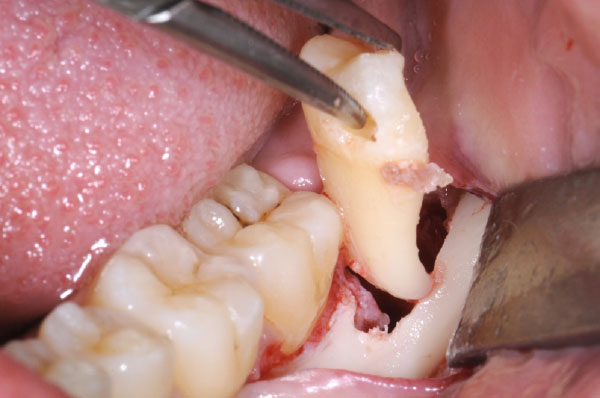

L'intervento segue precisi protocolli chirurgici. Dopo l'esecuzione di un'anestesia loco-regionale, si procede all'allestimento di un lembo di accesso mucoperiosteo a spessore totale, la cui scelta è determinata principalmente dalla profondità dell'inclusione e dalla posizione del terzo molare. In tutti i casi, il lembo deve creare un sufficiente accesso chirurgico (visivo e strumentale), evitare le strutture anatomiche circostanti (nervo linguale, arteria facciale), consentire un corretto riposizionamento del lembo e un'agevole sutura.

Poiché gli interventi di avulsione degli ottavi inferiori prevedono l'utilizzo di uno strumentario base per la chirurgia estrattiva e uno strumentario specifico per le manovre di ostectomia e odontotomia, sono anche forniti i criteri di scelta più adeguati per l'esecuzione dell'intervento, per la preparazione del paziente e dell'ambiente di lavoro.